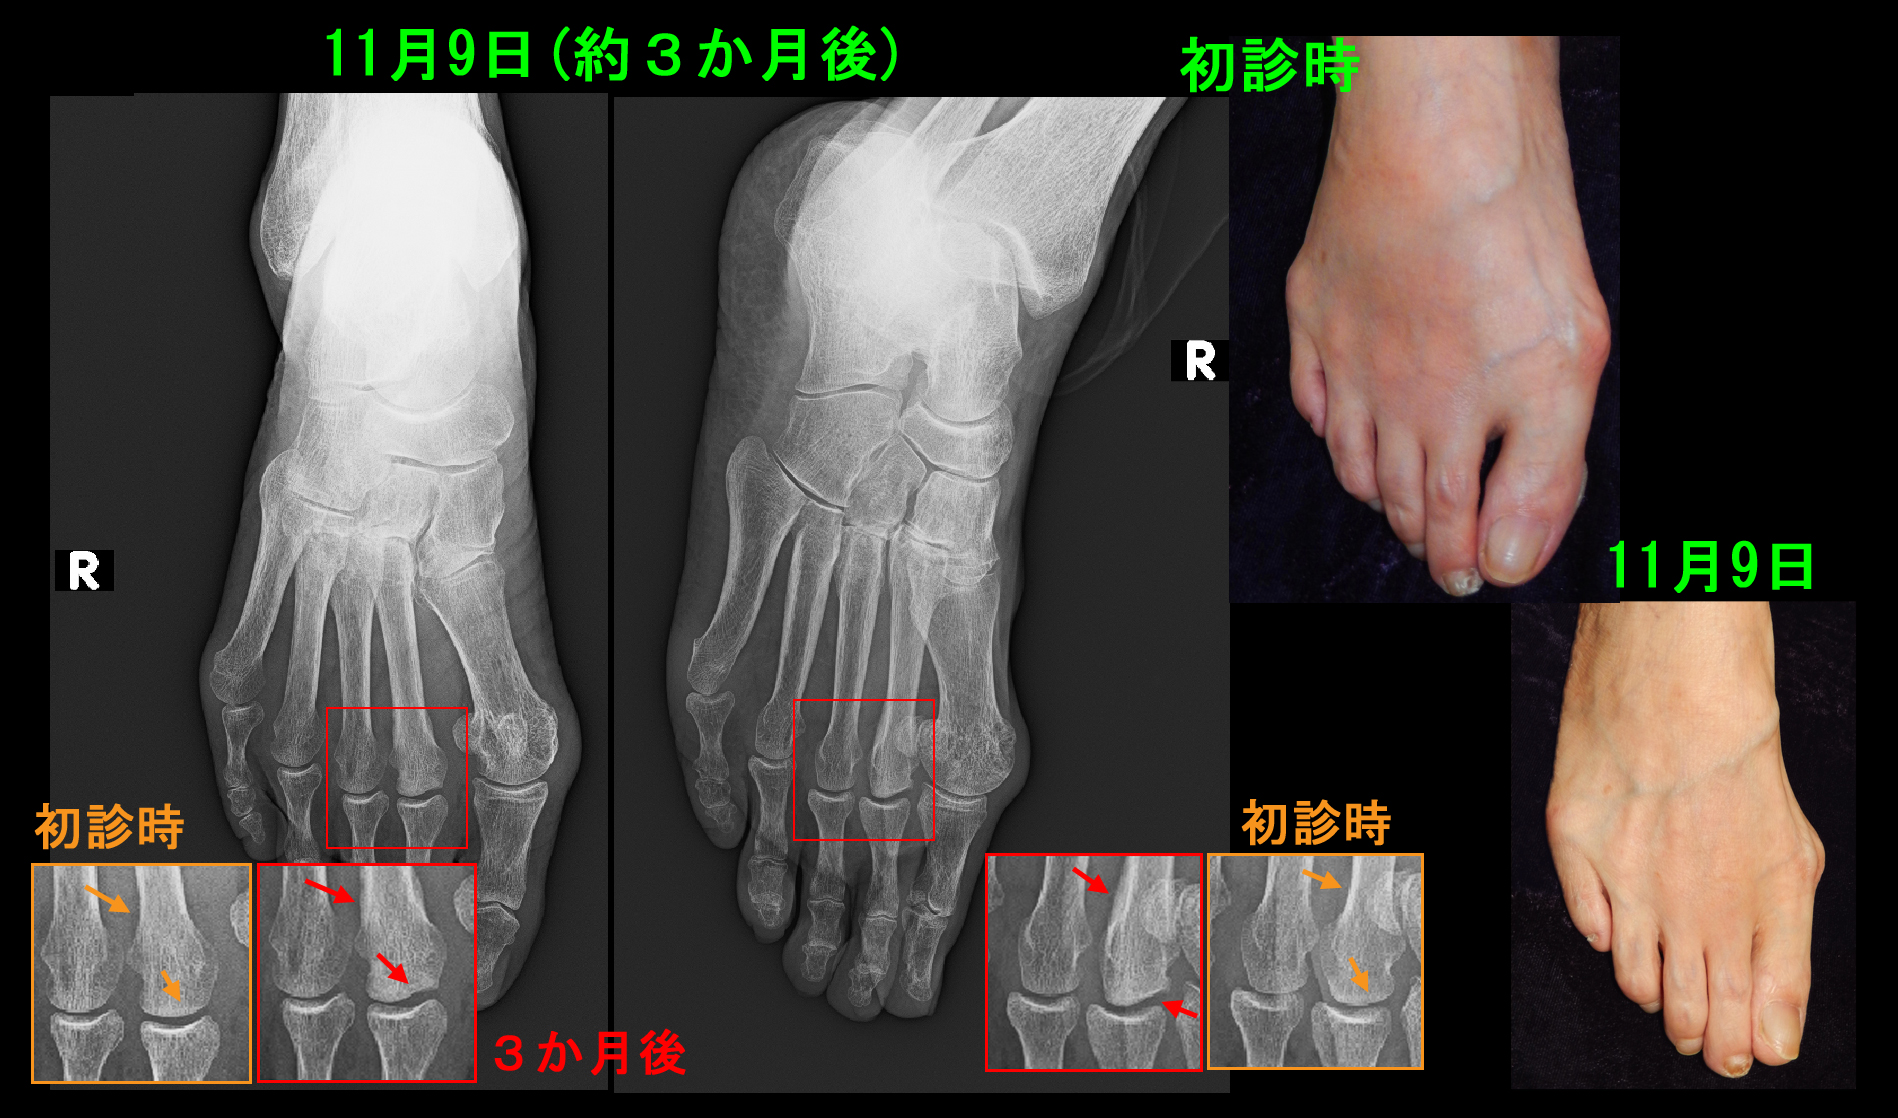

76才女 Xp2.jpg

11月9日にも腰痛で受診されていますが、その時の右足の状態とレントゲン像となります。初診時赤みを帯びて腫れていた右足は正常化しており、レントゲン像では第2中足骨に骨が形成されているのと、関節部分の一部に凹みが観察されます。骨の陥凹が起こるとともに骨形成が起こり治癒したと理解されます。